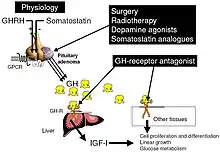

The goals of treatment are to reduce GH production to normal levels thereby reversing or ameliorating the signs and symptoms of acromegaly, to relieve the pressure that the growing pituitary tumor exerts on the surrounding brain areas, and to preserve normal pituitary function. Currently, treatment options include surgical removal of the tumor, drug therapy, and radiation therapy of the pituitary.

Medications

Somatostatin analogues

The primary current medical treatment of acromegaly is to use somatostatin analogues – octreotide (Sandostatin) or lanreotide (Somatuline). These somatostatin analogues are synthetic forms of a brain hormone, somatostatin, which stops GH production. The long-acting forms of these drugs must be injected every 2 to 4 weeks for effective treatment. Most people with acromegaly respond to this medication. In many people with acromegaly, GH levels fall within one hour and headaches improve within minutes after the injection. Octreotide and lanreotide are effective for long-term treatment. Octreotide and lanreotide have also been used successfully to treat people with acromegaly caused by non-pituitary tumors.

Dopamine agonists

For those who are unresponsive to somatostatin analogues, or for whom they are otherwise contraindicated, it is possible to treat using one of the dopamine agonists, bromocriptine or cabergoline. As tablets rather than injections, they cost considerably less. These drugs can also be used as an adjunct to somatostatin analogue therapy. They are most effective in those whose pituitary tumours cosecrete prolactin. Side effects of these dopamine agonists include gastrointestinal upset, nausea, vomiting, light-headedness when standing, and nasal congestion. These side effects can be reduced or eliminated if medication is started at a very low dose at bedtime, taken with food, and gradually increased to the full therapeutic dose. Bromocriptine lowers GH and IGF-1 levels and reduces tumor size in fewer than half of people with acromegaly. Some people report improvement in their symptoms although their GH and IGF-1 levels still are elevated.

Growth hormone receptor antagonists

The latest development in the medical treatment of acromegaly is the use of growth hormone receptor antagonists. The only available member of this family is pegvisomant (Somavert). By blocking the action of the endogenous growth hormone molecules, this compound is able to control the disease activity of acromegaly in virtually everyone with acromegaly. Pegvisomant has to be administered subcutaneously by daily injections. Combinations of long-acting somatostatin analogues and weekly injections of pegvisomant seem to be equally effective as daily injections of pegvisomant.

Surgery

Radiation therapy